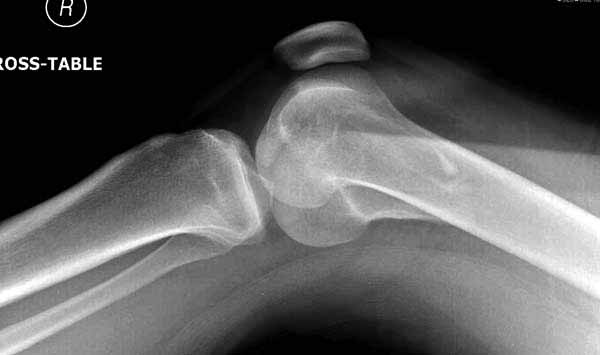

А теперь по поводу лечения перелома. Среди всех чрез/меж-мыщелковых переломов в 38% сопровождются переломом в корональной плоскости, т.е перелом Hoffa. Nork et al, J Orthop Trauma, 87:564, 2005.

По снимку вроде одиночный простой мыщелковый перелом, и такой внутрисуставной перелом не обязательно дистрагировать на скелетном вытяжении, потому что не не нарушается непрерывность колонны с одной стороны. И для таких простых переломов подойдет любой метод: 95 градусная пластина, Lat. Condylar Butress пластина или ретроградный гвоздь. А для особых энтузиастов которые желают антеградную фиксацию, возможно легко найти трохантер у алкоголиков или дистрофиков. А вот у откормленных Макдональдскими гамбургерами? Если поискать у них тоже можно найти, но стоит ли?

У больных как в этом случае, с вовлечением двух мыщелков правильно, что сделали вытяжение до операции. Здесь имеется флексионный компонент на другой стороне, и я бы рекомендовал операцию делать из двух доступов. Сперва фиксировать медиальную колонну custom made пластиной, обычно 1/3 тубулярной пластиной в 4.5 мм, потому что пока производители опаздывают с медиальной пластиной.